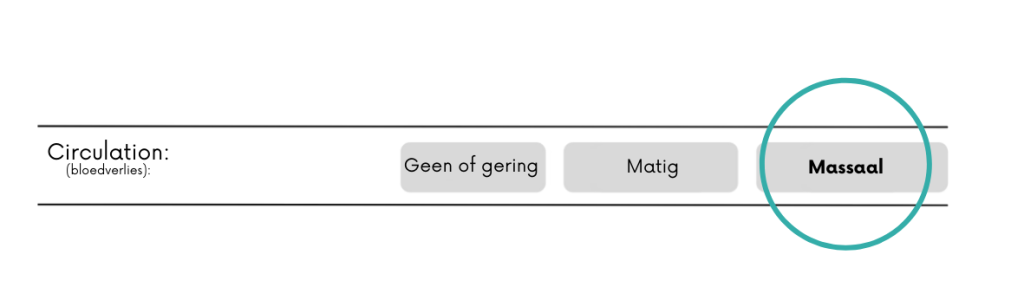

Nee/gering = geen bloeding of beetje sijpelen.

Matig = een bloeding die niet volledig onder controle is te krijgen door het uitoefenen van directe druk.

Massaal = bloed gutst met grote hoeveelheden eruit. Hieronder vallen ook grote hoeveelheden bloed braken of ophoesten.